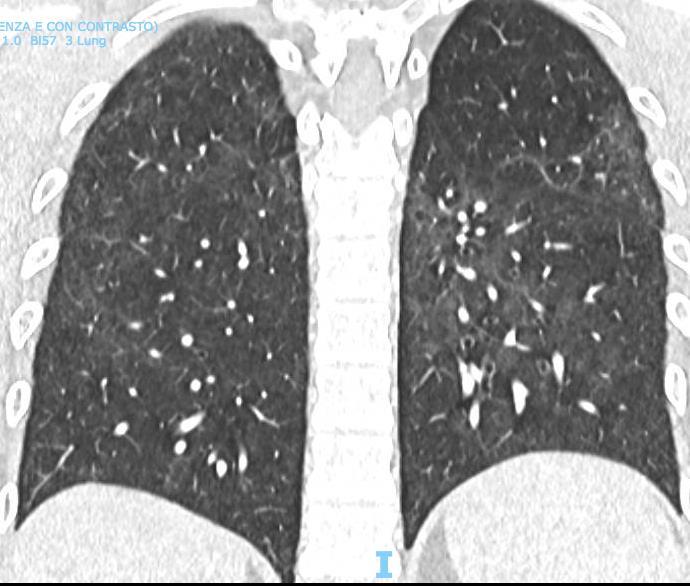

Acute Pediatric COVID-19: CT

21 Imaging of Covid 19 infection in children

3 Phases

Early: "Halo" sign

Local infection

Progressive: Diffuse GGO

Developed: Consolidation

Surr vasc congestion

Inflammation - adj alveoli

Alveoli fill with fluid/cells